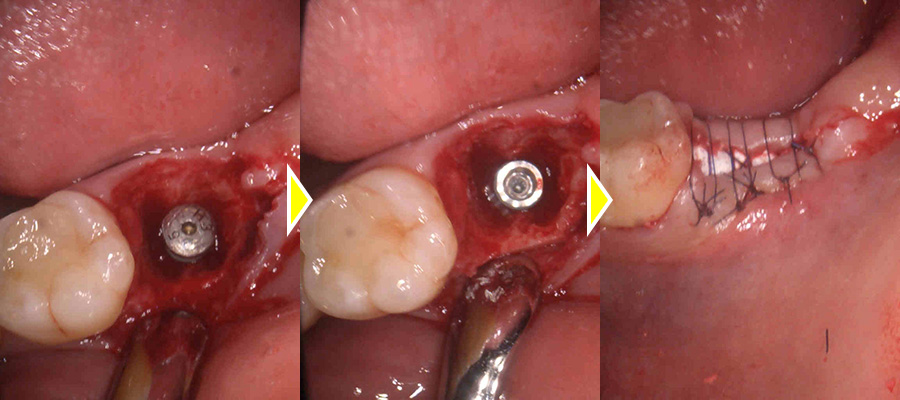

補綴除去後実際に破折線がみられたため予定通り抜歯、中の大きく広がっている膿の塊も取り出しました。

破折のため膿が大きく骨欠損の範囲が大きかったためインプラントの持ちを良くするため骨造成も同時に行っています。